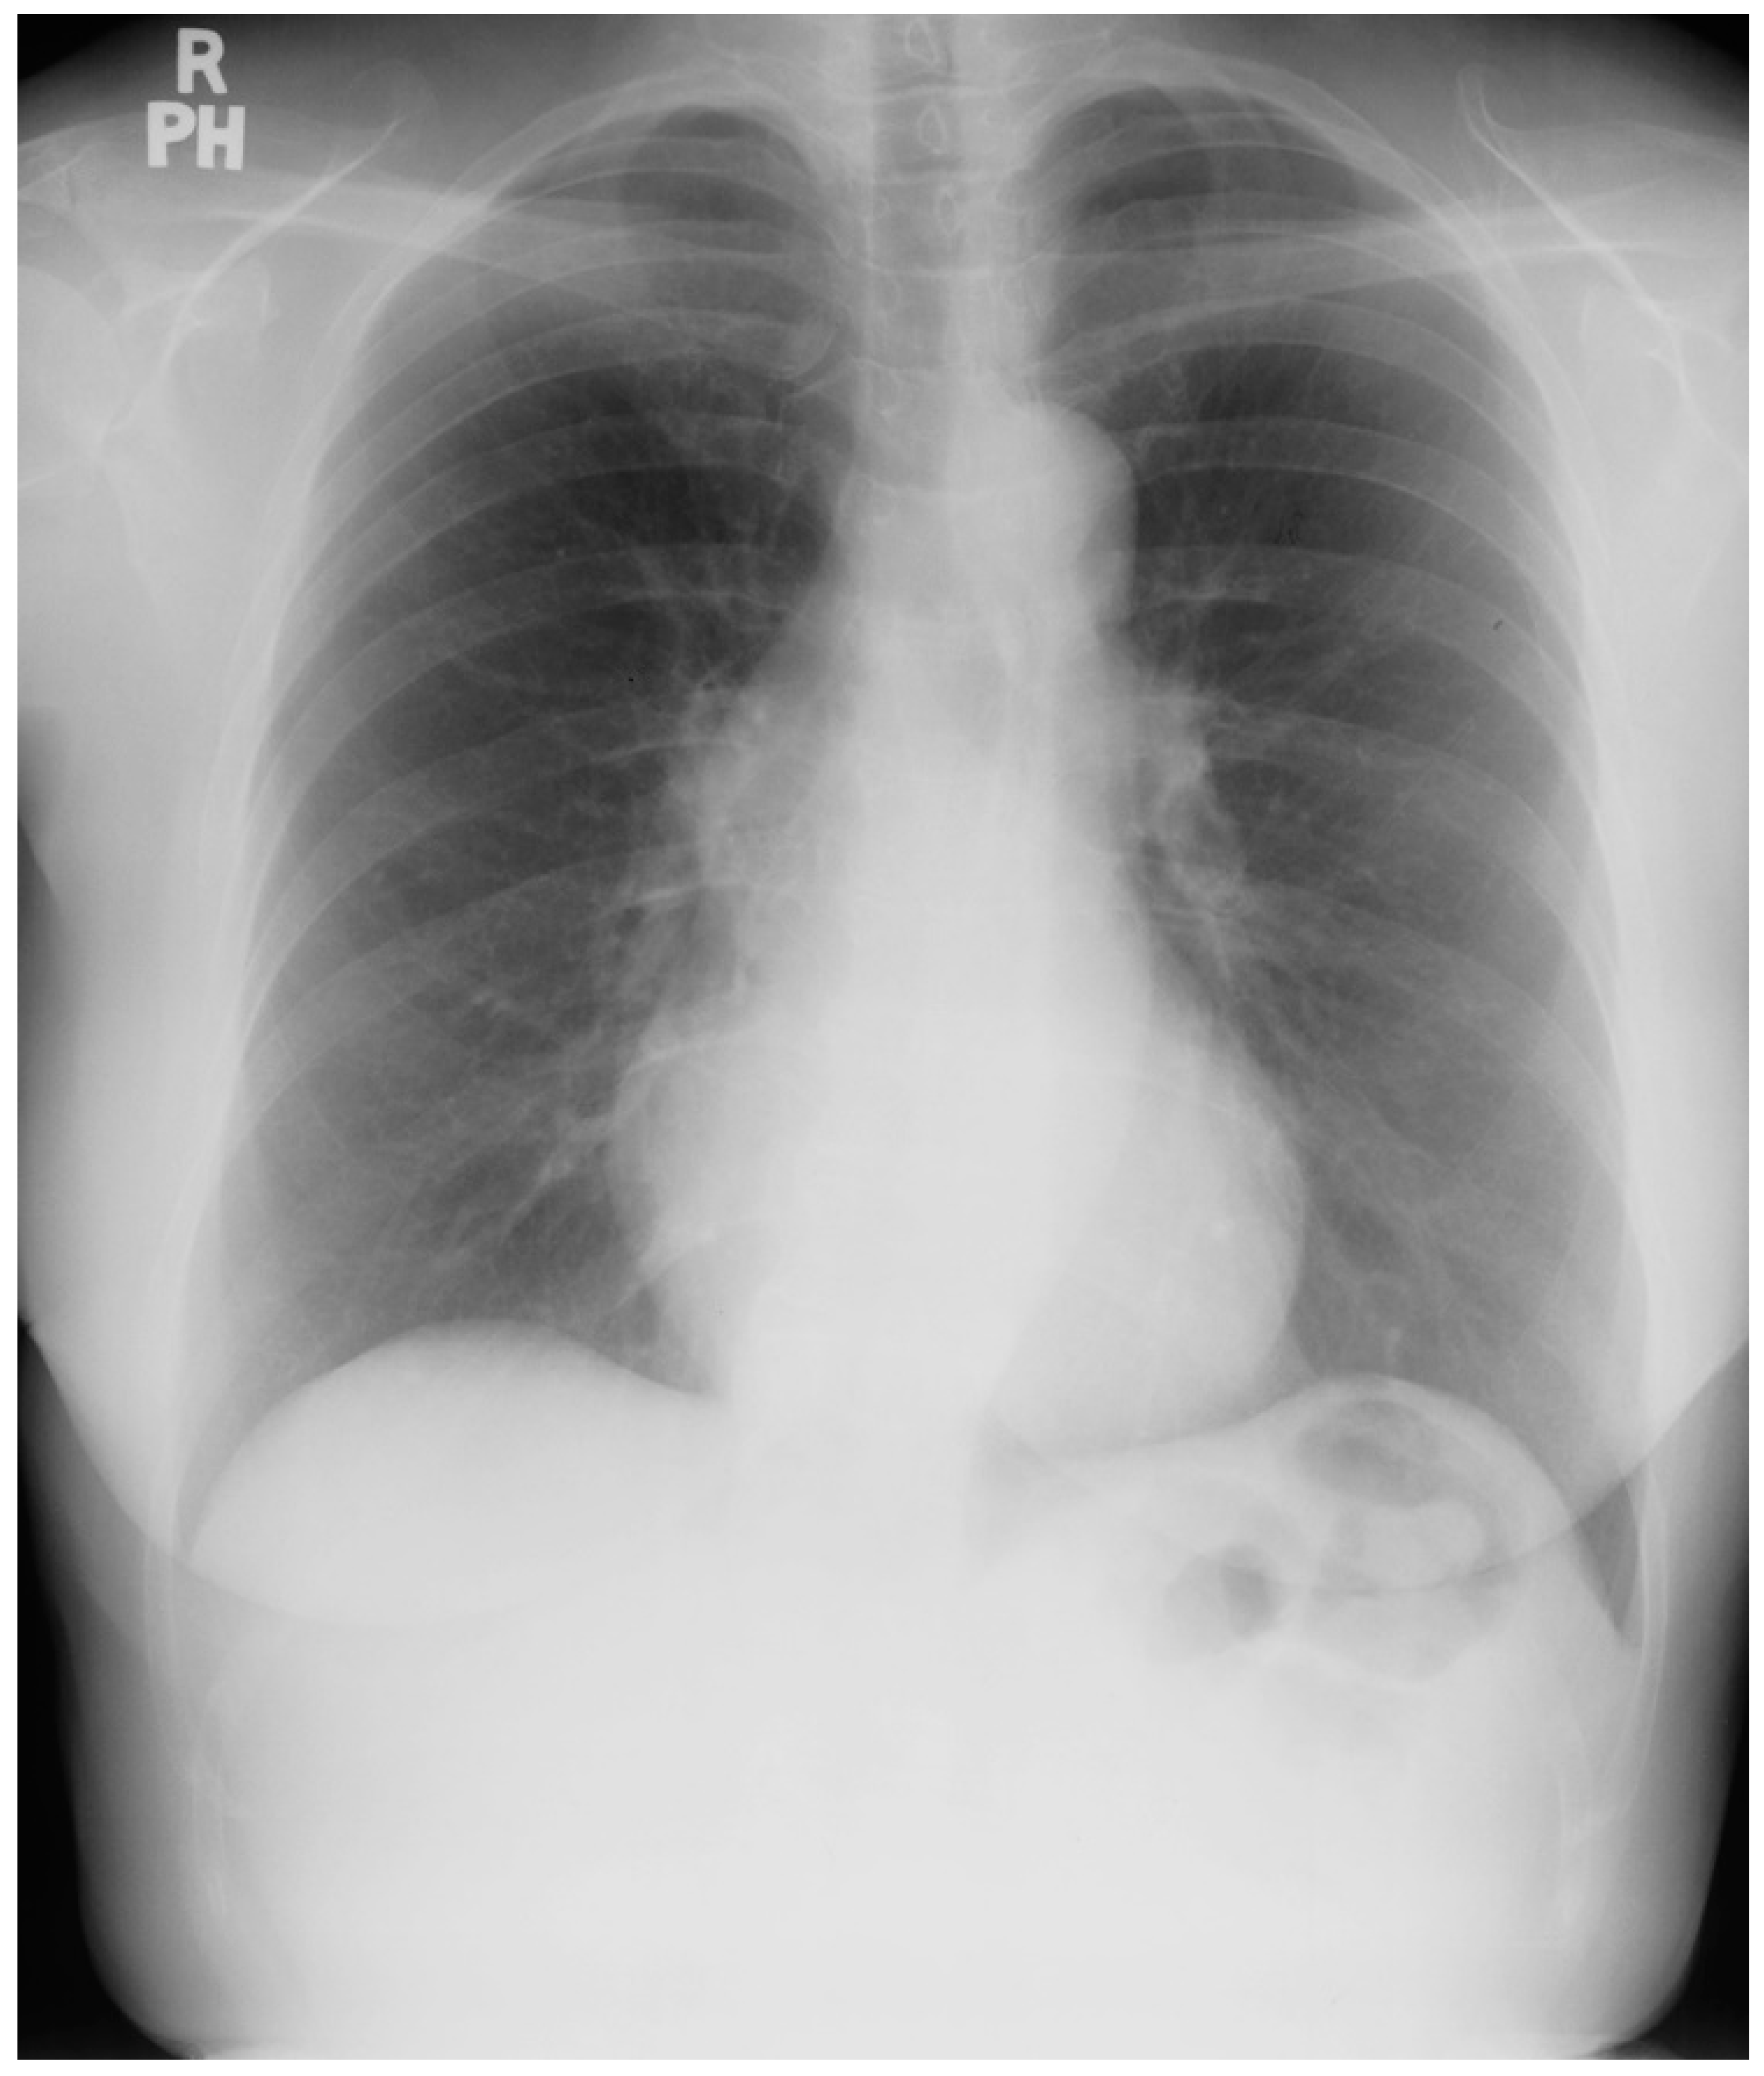

Figure 10.

Posteroanterior chest X-ray of ostium secundum atrial septal defect (OSASD): This is a chest X-ray of a 46-year-old male with an uncorrected OSASD. The image is slightly rotated. There is a good inspiration. The cardiothoracic ratio is increased. The pulmonary trunk is enlarged and there is a lateral rim of calcification. Compared to the enlarged central pulmonary circulation the more peripheral pulmonary vessels are much smaller (called pruning), suggesting pulmonary vascular obstructive disease. The lower right heart border demonstrates right atrial enlargement. The aortic knob is smaller than the pulmonary trunk, indicating a significant left to right shunt.